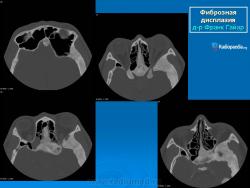

Локализация: для монооссальной фиброзной дисплазии характерно поражение одной из костей лицевого черепа, а также бедренной или большеберцовой кости, реже одного ребра; при полиоссальной фиброзной дисплазии страдают в первую очередь бедренная, большеберцовая и тазовые кости, не исключено и поражение мелких костей стопы, черепа, реже ребер. Рентгенологическая картина фиброзной дисплазии разнообразна. Патологические участки могут быть то более плотными, то более прозрачными по сравнению с окружающей костью, иногда имеют вид «матового стекла». Одни очаги четко отграничены зоной склероза, контуры других расплывчатые, что особенно характерно для костей черепа. Нередко выявляются узуры в кортикальном слое, а при наличии перелома — отчетливая периостальная реакция. При макроскопическом исследовании определяются беловато-красные опухолевые очаги разной плотности, в зависимости от степени выраженности их минерализации. Имеются многочисленные кисты, заполненные желтоватой или красноватой жидкостью, и полупрозрачные участки хряща до 3 см в диаметре.

Для фиброзной остеодисплазии, или болезни Брайцева-Лихтенштейна, характерно нарушение костеобразующей функции мезенхимы, проявляющееся в одной или нескольких костях, что ведет к их деформации и образованию в них очагов разрежения, обычно отграниченных от здоровой ткани кости склеротической каймой. Объем пораженной кости при этом может быть увеличен. Чаще поражаются трубчатые кости, но характерные изменения могут отмечаться и в костях черепа. В таких случаях возможны облитерация придаточных полостей носа, деформация глазниц, сужение отверстий в основании мозгового черепа и в лицевом черепе, ведущее к нарушению функции проходящих через них нервов и сосудов. Заболевание, возможно, наследственное, проявляется с детских лет. Описал в I927 г. отечественный хирург В.Р. Брайцев (1878-1964), несколько позже - американский патологоанатом L. Lichtenstein (1906-1977).